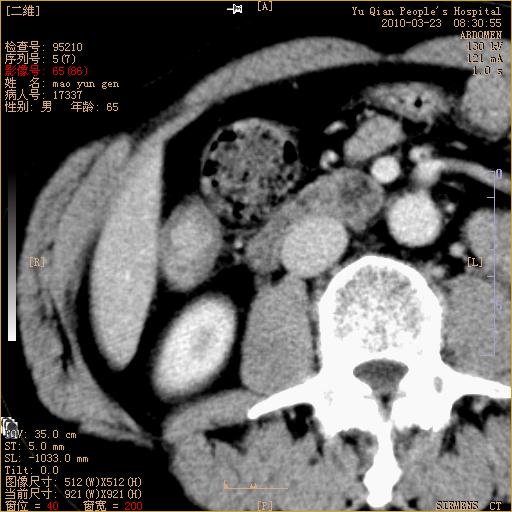

标题: CT25266:消瘦月余,前来肝部检查,请看看肠腔 [打印本页]

标题: CT25266:消瘦月余,前来肝部检查,请看看肠腔

肝区结肠占位,腺癌可考虑,建议肠镜活检。

升结肠肠壁增厚,不均强化,考虑升结肠腺癌可能性,建议肠镜检查。

1)考虑升结肠癌。2)右肾小囊肿。